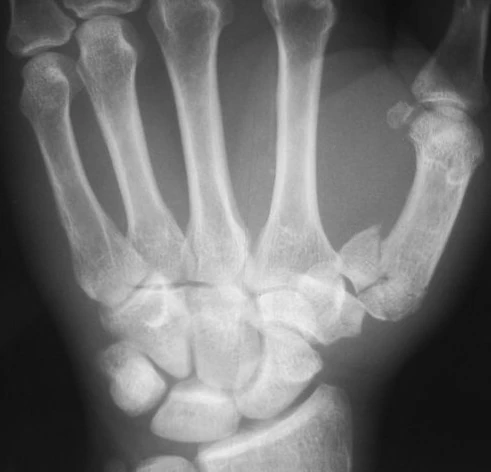

- Рентгенография кисти — является основным методом визуализации для выявления и классификации переломов основания первой пястной кости. Для получения полной картины повреждения и адекватной оценки состояния первого запястно-пястного сустава рекомендуется выполнение серии снимков, включающей переднезаднюю, боковую и косую проекции[3]. Для получения боковой проекции кисть пронируют на 15-25 градусов, а рентгеновские лучи направляют под углом 15 градусов. В сложных случаях дополнительно используют косой снимок, который позволяет уточнить детали перелома. При переломе Роландо на снимках определяется характерный Т- или Y-образный перелом, при котором основание пястной кости разделяется на тыльный и ладонный фрагменты[4].